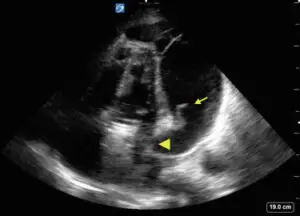

Apical 4 chamber view of the heart demonstrating a large circumferential complex pericardial effusion. Fibrin stranding is demonstrated beating with the atrioventricular valves. Signs of tamponade physiology are seen with both right ventricular and left ventricular collapse in diastole.

The patient was immediately taken to the operating room for a subxiphoid pericardial window for cardiac tamponade. Emergency physicians can use point-of-care ultrasound for the identification of pericardial effusions, which include states of profound shock and cardiac arrrest.1 The findings on point-of-care ultrasound that were suggestive of cardiac tamponade include the presence of a pericardial effusion with identification of cardiac chamber collapse (Fig).2,3 The specificity for tamponade goes up with progression of the chamber involved from the right atria and ventricle to eventually the left sided cardiac chambers.3 Collapse of the left atrium and ventricle can be seen in the apical 4 chamber clip. Postoperative tamponade can involve the left ventricle and is seen most frequently after valve surgery and in patients on anticoagulation.3,4